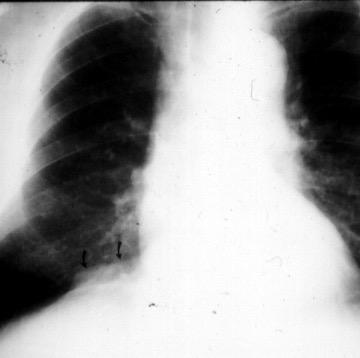

Accidente de tráfico

Rx: Niveles hidroaéreos en hemitórax izquierdo Desviación mediastínica Ausencia de intestino en abdomen. Configuración en reloj de arena del intestino herniado “Tubo nasogástrico”

Furak J et al. Diaphragm and transdiaphragmatic injuries. J Thorac Dis 2019